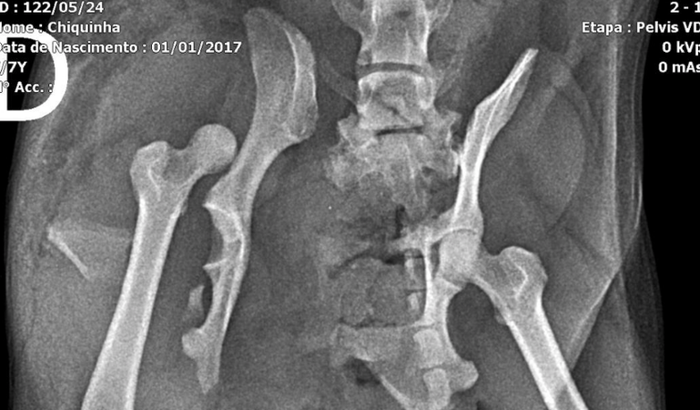

Chiquinha é uma pinscher caramelo de 7 anos. Porfavor nos ajude. Ela é da comunidade Borda do Mato(Grajaú) , seus tutores são Ivonete e Dely, duas pessoas muito conhecidas na comunidade. Ela foi atropelada por um carro no dia 26/05 e nessecita urgente de uma cirurgia, pois quebrou a pata e está sedada. O valor aproximado de tudo é de 3.000,00. Porfavor, Chiquinha precisa da nossa ajuda.